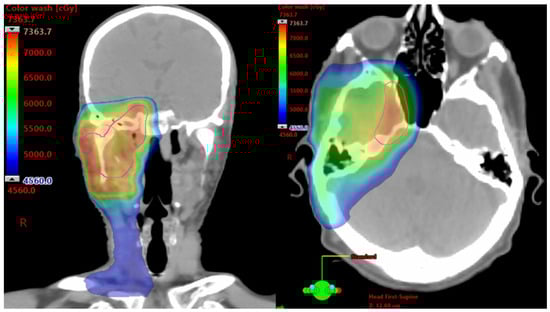

- Bryant, C.M.; Dagan, R.; Holtzman, A.L.; Fernandes, R.; Bunnell, A.; Mendenhall, W.M. Passively Scattered Proton Therapy for Nonmelanoma Skin Cancer with Clinical Perineural Invasion. Int. J. Part. Ther. 2021, 8, 285–293. [Google Scholar] [CrossRef]

- Holtzman, A.L.; Mendenhall, W.M. High-dose conformal proton therapy for clinical perineural invasion in cutaneous head and neck cancer. Oral Oncol. 2020, 100, 104486. [Google Scholar] [CrossRef]

- Baumann, B.C.; Mitra, N.; Harton, J.G.; Xiao, Y.; Wojcieszynski, A.P.; Gabriel, P.E.; Zhong, H.; Geng, H.; Doucette, A.; Wei, J.; et al. Comparative Effectiveness of Proton vs. Photon Therapy as Part of Concurrent Chemoradiotherapy for Locally Advanced Cancer. JAMA Oncol. 2020, 6, 237–246. [Google Scholar] [CrossRef] [PubMed]

- Bortfeld, T.R.; Loeffler, J.S. Three ways to make proton therapy affordable. Nature 2017, 549, 451–453. [Google Scholar] [CrossRef] [PubMed]